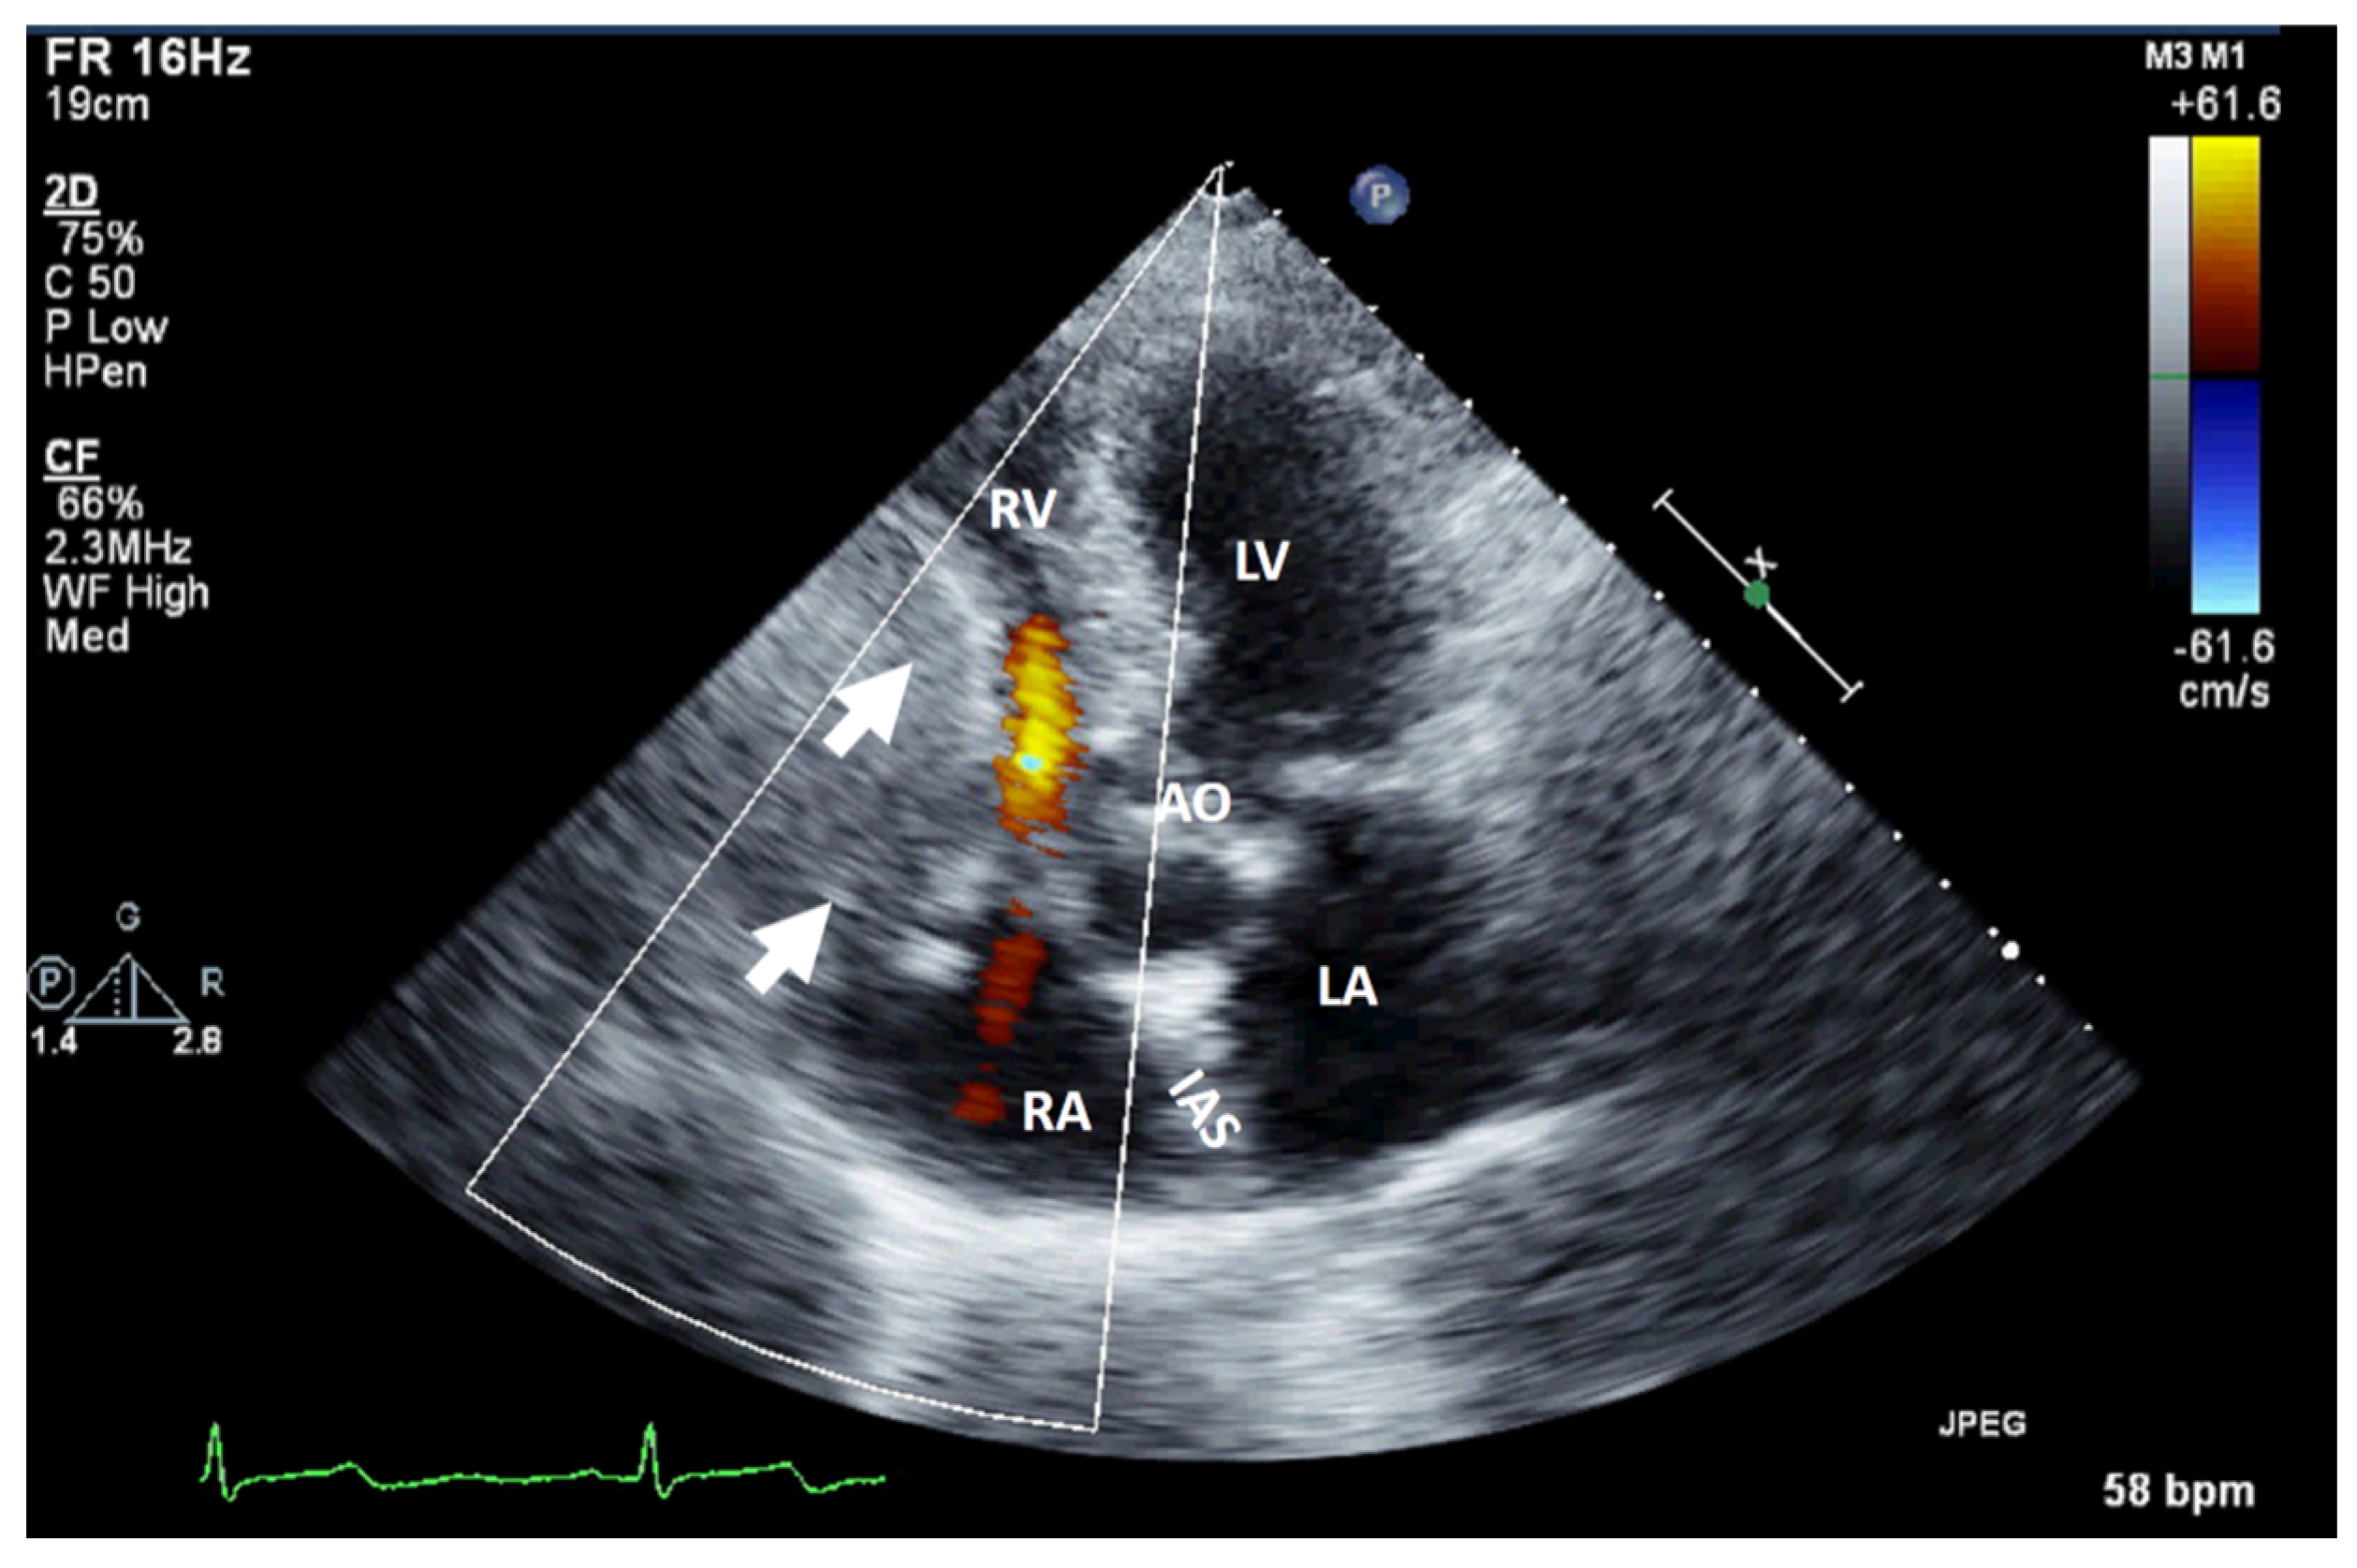

It can be used as a screening imaging method, but right heart tumors could be an incidental finding during a routine echocardiographic examination. This imaging technique is widely available (accessible), portable, and easy to perform, even at the patient’s bedside and in those who are hemodynamically unstable. It is safe, repeatable, cost-effective, and has a good spatial resolution (higher with TEE) and an excellent temporal resolution. For imaging small, highly mobile masses (<1 cm) or masses arising from valves, it is the optimal imaging modality [4]. TEE is more sensitive at identifying tumors smaller than 5 mm compared with TTE. Therefore, compared with TTE, TEE is better for the detection, location, and mobility of cardiac tumors and equivalent in the assessment of hemodynamic impact, compromising the compression/destruction/distortion of cardiac structures [12]. In some cases, the mass effect of a non-cardiac tumor severely compromises cardiac hemodynamics (Figure 1).

Figure 1.

Two-dimensional transthoracic echocardiography (apical 4-chamber view) with color Doppler showing external compression of the free right ventricular wall (arrow) in a patient with hepatomegaly due to a hepatic tumor, which explains hemodynamic instability (similar to a localized cardiac tamponade). AO, aorta; IAS, interatrial septum; LA, left atrium; LV, left ventricle; RA, right atrium; RV, right ventricle.